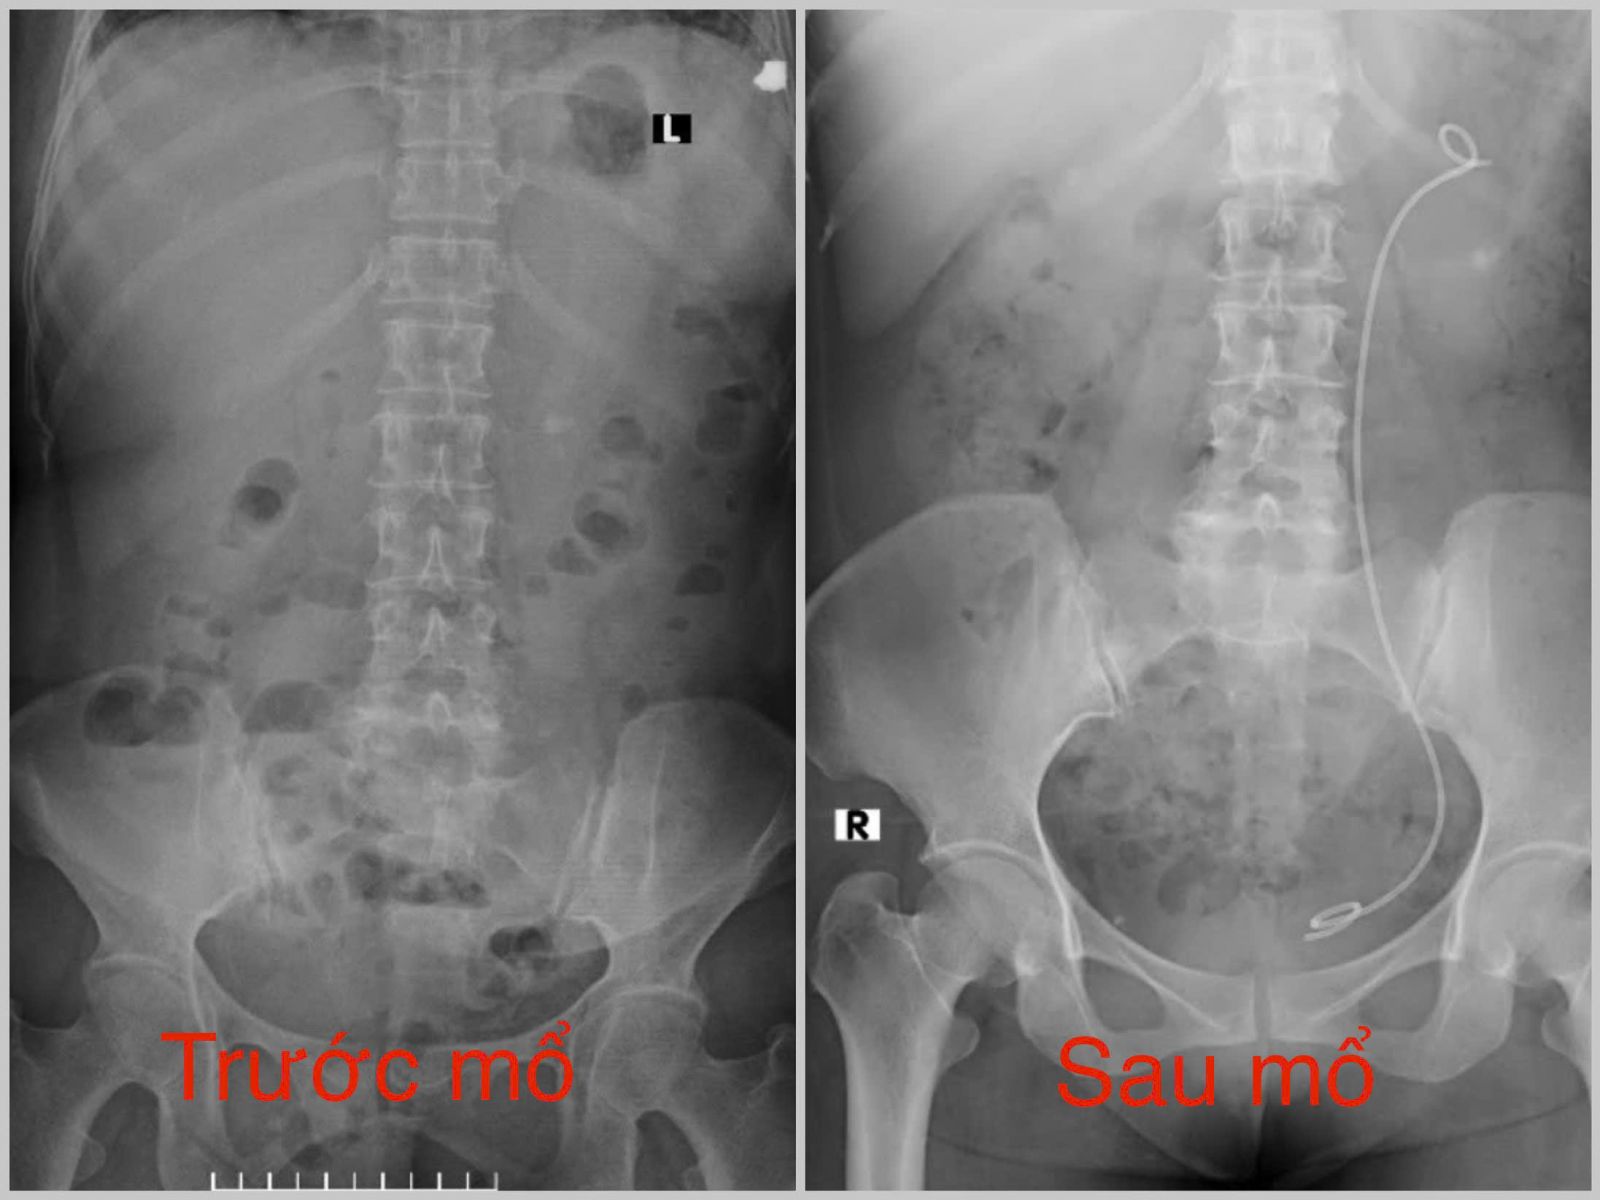

Kết quả chụp CT-Scanner hệ tiết niệu cho thấy hình ảnh hẹp niệu quản trái 1/3 trên kèm sỏi niệu quản và sỏi hai thận, bạch cầu và CRP tăng cao, nguy cơ nhiễm khuẩn huyết cận kề. Xác định đây là trường hợp ứ mủ thận trái do sỏi và hẹp niệu quản, kíp phẫu thuật đã can thiệp nội soi cấp cứu nong niệu quản, đặt sonde JJ giải phóng tắc nghẽn, bảo tồn chức năng thận.

Sau phẫu thuật, các chỉ số viêm giảm nhanh, tình trạng bệnh nhân dần ổn định. Đến ngày 09/10, bệnh nhân hồi phục và được xuất viện.